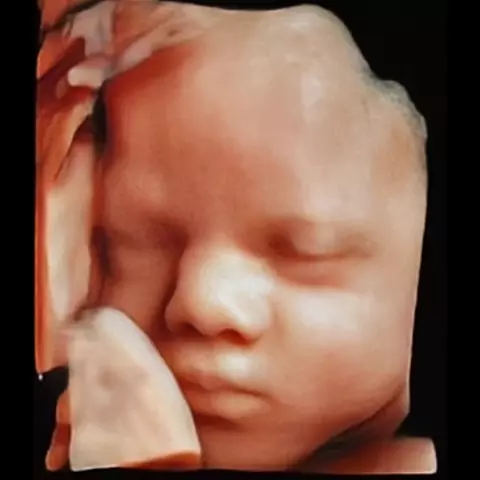

ÚNICA diag por imagem

#diagnostico #ultrassommorfologico #jundiaieregiao #diagnosticoporimagem #ultrassom3d sp